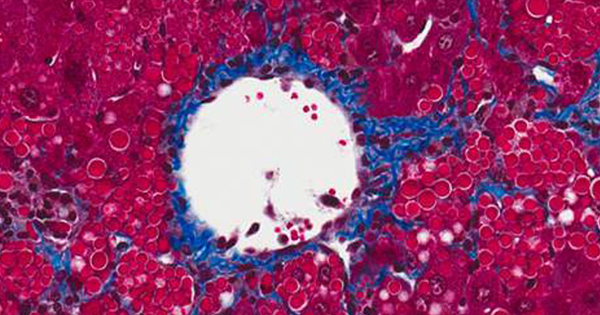

More About Our Research on Alpha-1 Antitrypsin Deficiency